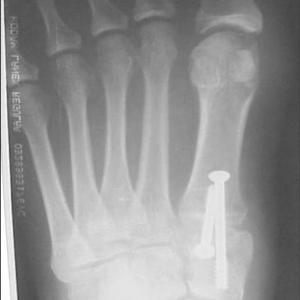

This is a typical illustration of the postoperative findings with a midfoot fusion/Lapidus type of bunionectomy. This is for moderate to severe bunions with a larger intermetatarsal (angle between 1 and 2) angle. Note the 2 sesmoid bones are realigned under the head of the metatarsal as they should be normally.